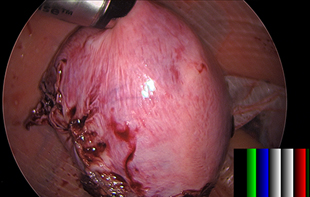

Background: 50-year-old patient who is Para 2 (1 caesarean section, 1 vaginal delivery) with normal cervical screening tests. The patient was referred with heavy and painful periods, ultrasound showed fibroid bulky uterus. The patient is known to have a history of hydrocephalus requiring ventriculoperitoneal shunt. The shunt can be seen with the laparoscopy images.

Procedure: Laparoscopic subtotal hysterectomy, bilateral salpingectomy (removal of both tubes), morcellation of uterus in Espinar bag (cutting the uterus into small pieces in a contained bag to achieve keyhole approach), and cystoscopy (camera in the bladder).

Findings: A large fibroid uterus measuring about 16–18-week size uterus, right ovarian cyst. The ventriculoperitoneal shunt was seen in the peritoneal cavity.

Histopathology results: The uterus measurements were 11.5, 11 and 4cm. There was a right ovarian cyst that was removed at the same time. Histology of the uterus confirmed benign fibroids with calcification.